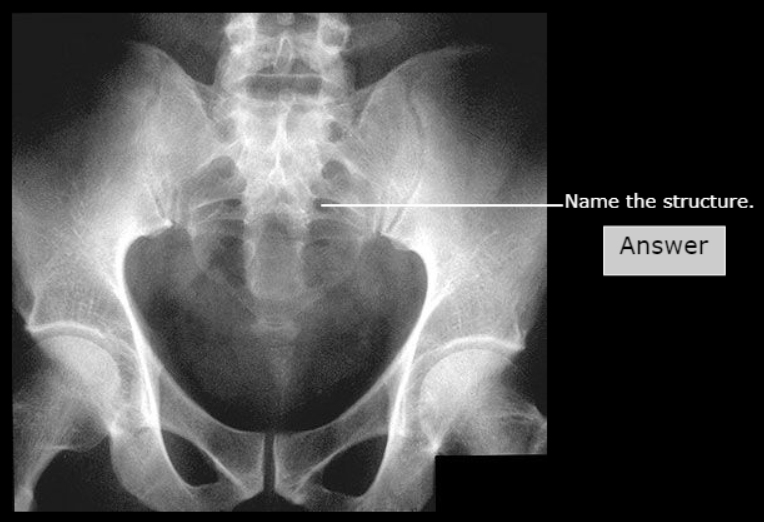

Sacrum